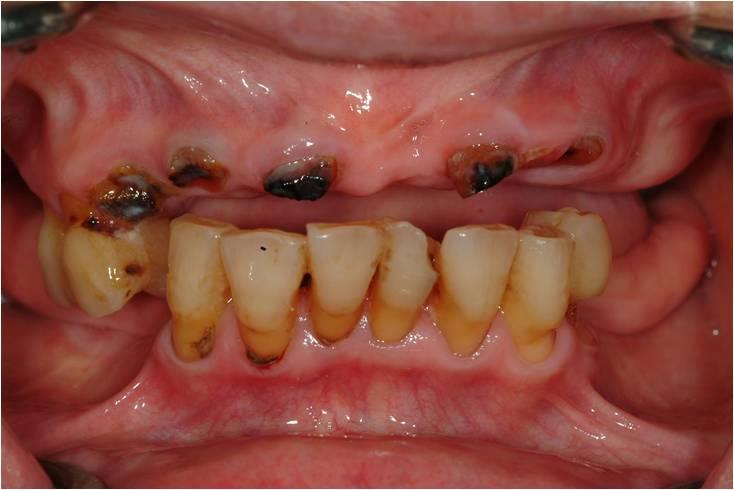

上の方の患者さんが感じる問題点は、

- 上の前歯がむし歯ですべて折れてしまった事(見た目)

- 奥歯がすべてかみ合わない事(機能)

- 残っている歯が伸びてシミてしまっている事(痛み症状)

- しゃべりずらくなっている事(発音)

①腐食してしまった歯が歯ぐきの中に埋まっている

むし歯や歯周病の原因菌は血中に入り込み、知らぬ間に全身をむしばみます。目に見えなく健康診断でも見落とされますので、原因となる細菌は除去することが病気の予防となります。つまり黒くなってしまっている根は抜歯する必要があります。

②シミる症状が出ている歯の神経の治療

シミる症状が強い場合噛むこともできなくなります。また歯ブラシを当てずらくなるため清掃状態が悪くなります。必要に応じて神経を取る処置が必要となります。

③残っている歯がぐらついている

動いてしまうほど歯周病が進行しているということは、既に無くなってしまっている所をこれから永く支えることはできません。さらに根の先まで歯周病菌が侵入しているはずなので、それを取り除くことは不可能となりますので、総合的に考えて抜歯となるかもしれません。